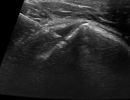

Η τεχνική PRP περιλαμβάνει τη λήψη μίας μικρής ποσότητας αίματος του ασθενούς, το οποίο φυγοκεντρείται ώστε να διαχωριστεί το πλάσμα που είναι πλούσιο σε αιμοπετάλια. Το προκύπτον πλάσμα εγχέεται, με την καθοδήγηση υπερήχου, στο σημείο της βλάβης.

Η καθοδήγηση υπερήχου κατά την ενέσιμη θεραπεία PRP αποτελεί κρίσιμο παράγοντα για την ακρίβεια και ασφάλεια της διαδικασίας.

Με τη δυνατότητα παρακολούθησης της βελόνας σε πραγματικό χρόνο, εξειδικευμένος Ιατρός-Ακτινολόγος μπορούν να καθορίσει με απόλυτη ακρίβεια την περιοχή όπου πρέπει να γίνει η ένεση. Αυτό εξασφαλίζει ότι η εισαγωγή του PRP θα γίνει ακριβώς στην επιθυμητή θέση, αποφεύγοντας γύρω ιστούς, νεύρα και αιμοφόρα αγγεία.

Η χρήση της υπερηχογραφίας όχι μόνο μειώνει τον κίνδυνο επιπλοκών, αλλά βελτιώνει και τα αποτελέσματα της θεραπείας, καθώς η ένεση διενεργείται με ακρίβεια στην πάσχουσα περιοχή, και όχι κατά προσέγγιση.